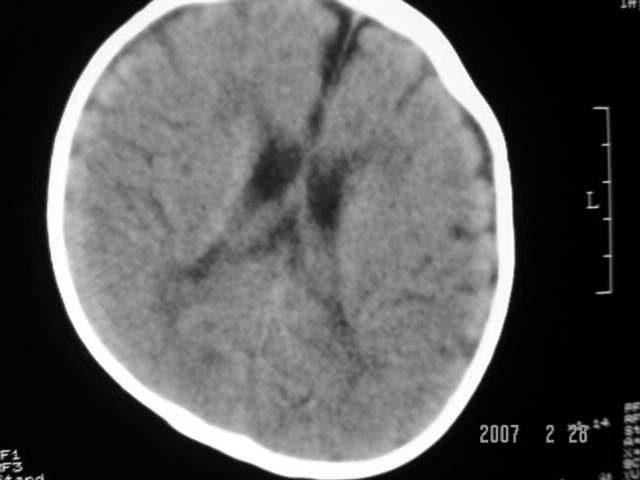

标题: PED0015:男,8M,发现不会坐立及神情异常,前囟已闭,双眼斜视, [打印本页]

标题: PED0015:男,8M,发现不会坐立及神情异常,前囟已闭,双眼斜视,

脑回较深,白质范围小,灰白质比例失调。余未见明显异常。

考虑:脑白质发育不良,必要时请做mri进一步检查。